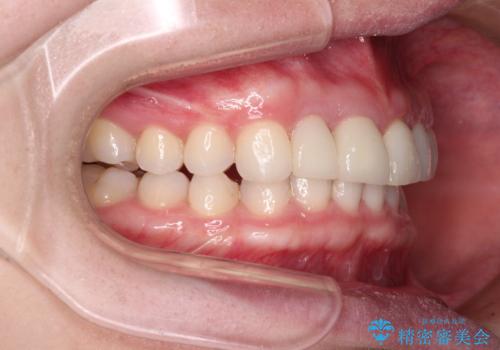

治療前、下顎前歯はほとんど見えない咬み合わせでしたが、矯正治療によりディープバイトが改善されました。

矯正治療中に前歯2本のクラウンは外れてしまい、途中仮歯に替える必要があったので期間は掛かりましたが、歯列も整い、負担のかからない咬み合わせを達成することができました。